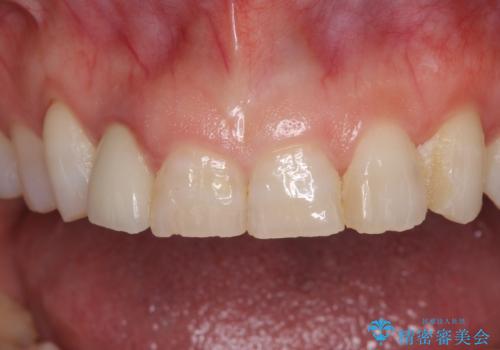

歯肉が腫れている前歯 外科処置を併用したオールセラミッククラウン

- 前歯のクラウン周りに歯肉が腫れていることを気にして来院された患者様です。

元々磨き残しによる歯肉の腫脹がありましたが、クラウンが歯肉深くに装着されていたため、特に腫脹が目立っていました。

仮歯に置き換えた際に歯周外科処置を行い、歯肉の腫脹が落ち着いたことを確認してオールセラミッククラウンにて補綴することとしました。

外科処置後の痛みを気にしていましたが、小規模の処置であったため、痛みを感じることはほとんどありませんでした。

気になっていた腫脹がなくなり、患者様には大変満足していただきました。